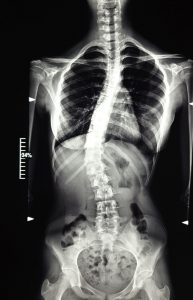

Kinetoterapia în scolioză și cifoză

Metoda tridimensională Schroth

Pacientul scoliotic va beneficia de o terapie adecvată, care înțelege și respecta mecanismul patogenic.

Terapia Schroth este o metoda de corecție posturală 3D activă combinată cu respirație rotațională și corecția percepției posturale.

Metoda a fost dezvoltată de Katharina Schroth în 1920, o doamnă care suferea de scolioză și care a încercat să-și corecteze propria deformare. Inspirată de modul în care este umflat un balon, a inițiat și antrenat respirația în părțile concave ale trunchiului din fața unei oglinzi.

Ea a conștientizat corectarea posturală 3D cu o serie de exerciții corective menite să susțină o postură corectată și a reusit sa schimbe percepția posturală a persoanei care suferă de scolioză.

Datorită succesului, metoda a căpătat atenție la nivel internațional, fiind una din cele mai studiate și utilizate metode în abordarea scoliozei idiopatice.

Astfel dar, astăzi, noi deținem o varianta actualizată și documentată științific.

Metoda Schroth stopează și chiar reduce curbura scoliotică, îmbunătățește aspectul estetic al spatelui, creste capacitatea respiratorie, previne intervenția chirurgicală.

Un alt avantaj al acestui program constă în aplicarea lui in cadrul activităților zilnice obișnuite, în scopul adoptării posturilor corective ce au ca efect reduce progresiei și a durerii, ceea ce permite pacienților să petreacă mai mult timp în activități de agrement și să ducă o viață normală.